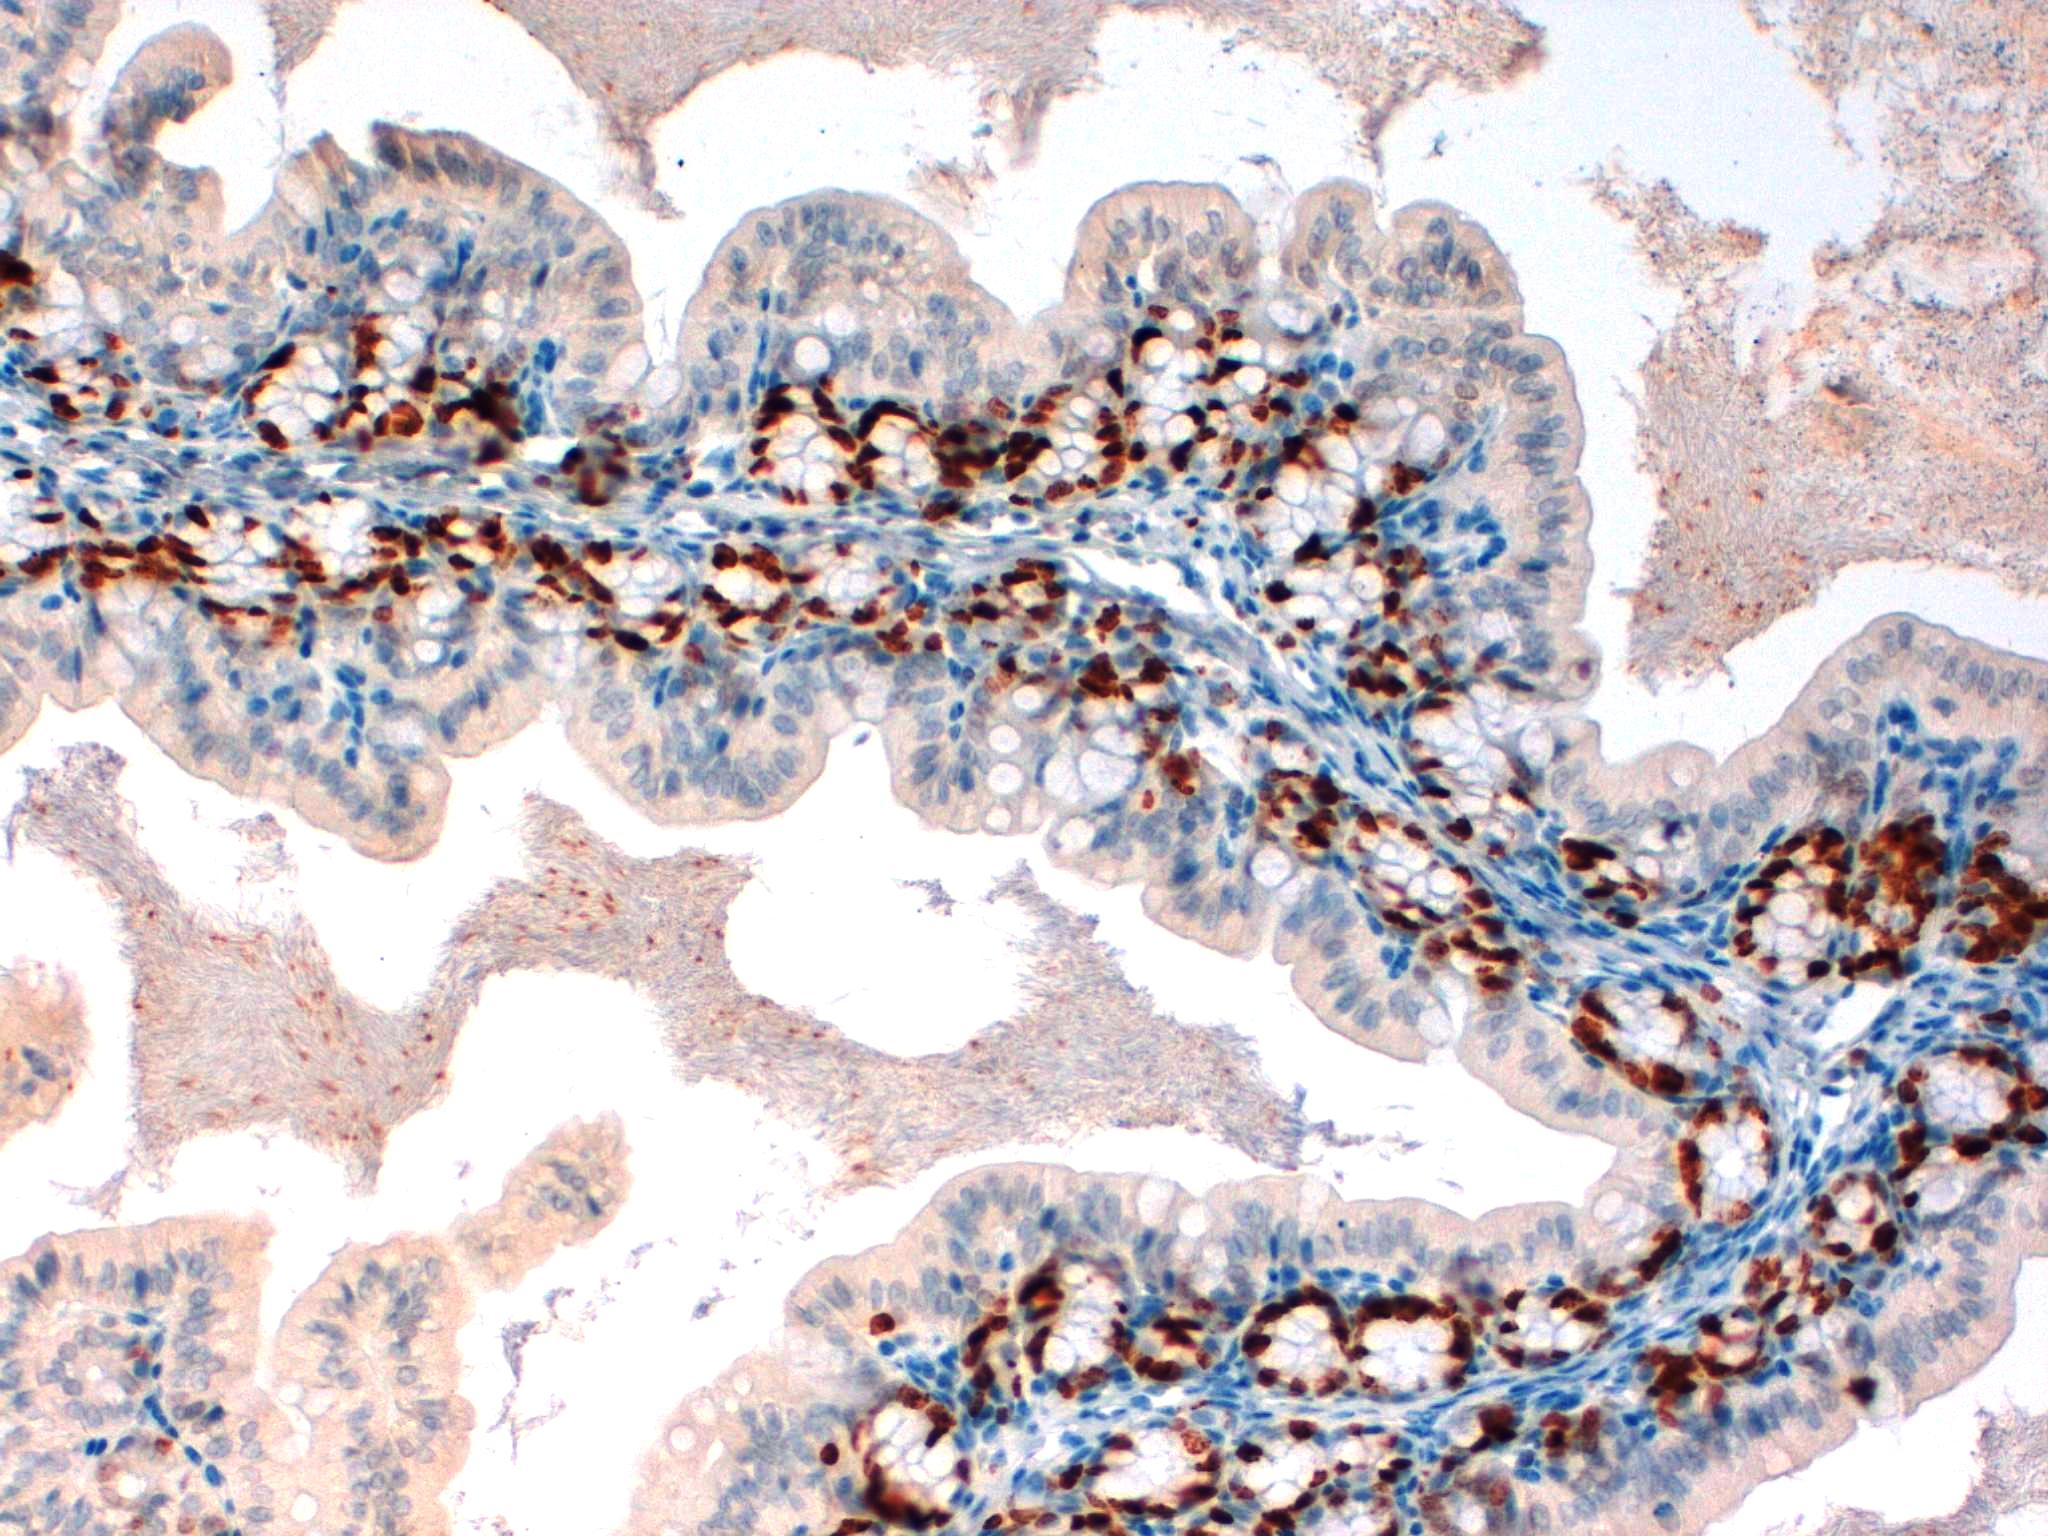

KI67 Mouse Intestine 20X

KI67 Mouse Intestine 10X